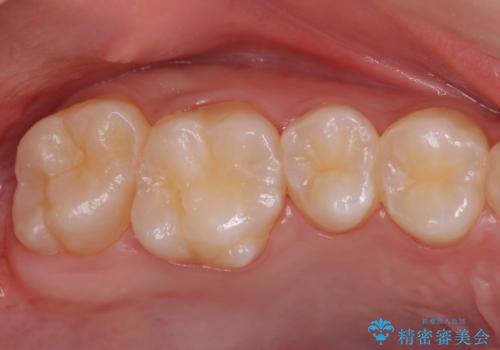

歯と歯の間の虫歯 セラミックインレーでの治療

- 検査の結果、レントゲン画像上で虫歯が確認されたため治療をしていくこととなりました。

白くて精度の高いものをご希望されたためセラミックインレーでの治療を行いました。

- 右上6 セラミックインレー 77,000円費用は治療当時の料金となります

小さな段差もないような適合の良い修復物は他の修復物に比べて今後の虫歯リスクを抑えることができます。